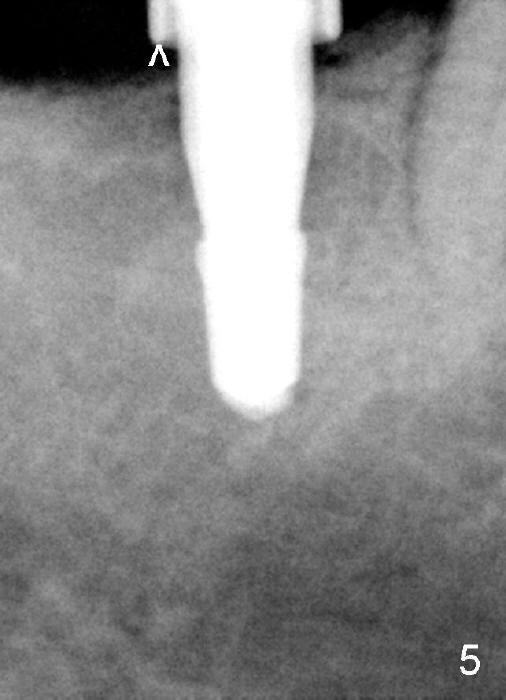

A 57-year-old lady returns for #31 implantation. The vertical edentulous space is limited, as the opposing tooth is supraerupted (Fig.1 arrow). Preop PA is critical (Fig.2), since it is used to measure the bone height (Fig.3: 12 mm). The length of the implant is expected to be 10 mm. The initial osteotomy depth is 8 mm (Fig.4); it appears that the trajectory should be adjusted. Osteotomy increases following depth and angulation adjustment (Fig.5: 4.5x10 mm drill). The submerged implant (5.3x10 mm) is placed with insertion torque approximately 35 Ncm (Fig.6). The buccal microthreads are exposed (Fig.7); to prepare for bone graft, the buccal plate is decorticated. Following placement of freeze dry mineralized allograft, collagen membrane is fixated by a healing screw (Fig.8). The incision is closed by 4-0 Chromic gut sutures and perio glue (Fig.9).